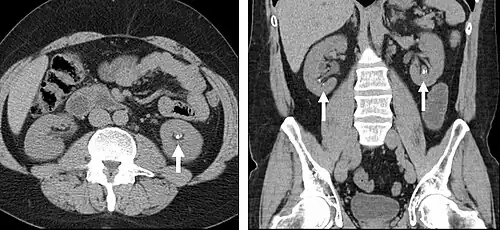

FIGURE 7. Selected images from a renal mass specific protocol CT. Corticomedullary phase (axial 7a) demonstrates peripheral enhancement of the renal cortex with minimal opacification of the renal medulla. There is a large renal cell carcinoma in the left kidney (right in image) which can be differentiated from the normal renal parenchyma by the heterogeneous and differential enhancement. The renal artery and vein are opacified in this phase as well. The collecting system is not opacified (coronal reformat 7b). In the parenchymal phase, the renal cortex and the medulla are enhancing. The renal cell carcinoma in the left kidney is not as well defined when compared to the corticomedullary phase images, but is actually slightly more conspicuous. There is some contrast noted within the collecting system during this phase (7c).

Detection and characterization of renal parenchymal masses is a frequent indication for CT. An initial noncontrast CT is important for detecting calcium or fat in a lesion, and to provide baseline attenuation of any renal masses. Following noncontrast scanning, intravenous contrast is injected and a corticomedullary phase is obtained at approximately 70 seconds (figure 7a, 7b). The corticomedullary phase is characterized by enhancement of the renal cortex as well as the renal vasculature. This phase is valuable in the evaluation of benign renal variants, lymphadenopathy and vasculature, however certain medullary renal masses may not be visible during this phase due to minimal enhancement of the medulla and collecting system. The parenchymal phase is obtained approximately 100–200 seconds after the injection of contrast material (figure 7c). Parenchymal phase imaging demonstrates continued enhancement of the cortex, enhancement of the medulla, and various levels of contrast material in the collecting system. The parenchymal phase is highly important for the detection and characterization of renal masses, parenchymal abnormalities, and the renal collecting system. This method of imaging does not evaluate for abnormalities of the collecting system.

Common renal masses can occasionally be differentiated from each other using this imaging technique. Renal cell carcinomas and oncocytomas typically demonstrate intense heterogeneous enhancement on the parenchymal phase images and cannot be reliably differentiated from each other but can be distinguished from other renal masses. Angiomyolipomas (AML's) also demonstrate intense contrast enhancement but characteristically contain macroscopic fat which can be detected on the noncontrast images, and can help to differentiate AML's from renal cell carcinomas and oncocytomas. Renal lymphoma on the other hand, will often have decreased enhancement when compared to the renal parenchyma on the parenchymal phase images.